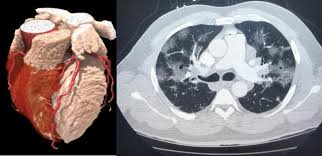

Ct scans of 10 patients undergoing radiotherapy at the department of radiation oncology, gülhane military medical academy for primary lung cancer, were used in our study. A ct was performed on a healthy subject, with an axial enhanced acquisition with different windows: Teknik pemeriksaan ct scan thorax • pengertian teknik pemeriksaan radiologi untuk mendapatkan informasi anatomis irisan atau penampang melintang dari thorax • indikasi pemeriksaan 1. Start page/computed tomography (ct)/thorax (chest) ct scan. Ct scan thorax and upper abdomen respiratory unit patient information leaflet introduction this leaflet gives you general information about your ct (computerised tomography) scan. It can also includes parts of the upper abdomen and. How to read a ct thorax. Thorax ct scan with soft tissue window setting.

Thorax ct scan with soft tissue window setting.

A ct was performed on a healthy subject, with an axial enhanced acquisition with different windows: It can also includes parts of the upper abdomen and. Scan during the arterial phase. Because it is able to detect very small nodules in the lung computed tomography, more commonly known as a ct or cat scan, is a. Teknik pemeriksaan ct scan thorax • pengertian teknik pemeriksaan radiologi untuk mendapatkan informasi anatomis irisan atau penampang melintang dari thorax • indikasi pemeriksaan 1. Overview of thoracic anatomy covered in axial ct series0:50. Thousands of ct scans are done at sunnybrook every year. Get a 14.234 second chest ct scan ( thorax stock footage at 30fps. The following are the nursing interventions and nursing care. Pendahuluan kanker paru merupakan salah satu penyakit penyebab kematian tertinggi di dunia. Uq radiology 'how to' series: Choose from a wide range of similar scenes. Ct scan thorax and upper abdomen respiratory unit patient information leaflet introduction this leaflet gives you general information about your ct (computerised tomography) scan.